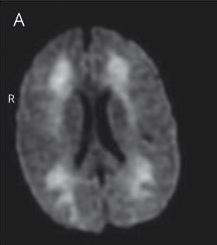

Toxic Leukoencephalopathy in a 45-year-old Female Opioid User

Diagnosis: Toxic Leukoencephalopathy due to Opioid Use (Heroin/Morphine/Oxycodone)

Certainty: Certain

Author: Dr. Atif Hussain

Date Published: Mar 24, 2026

Disease Specialty: Neurology

Image Type:

MRI

Histopathology